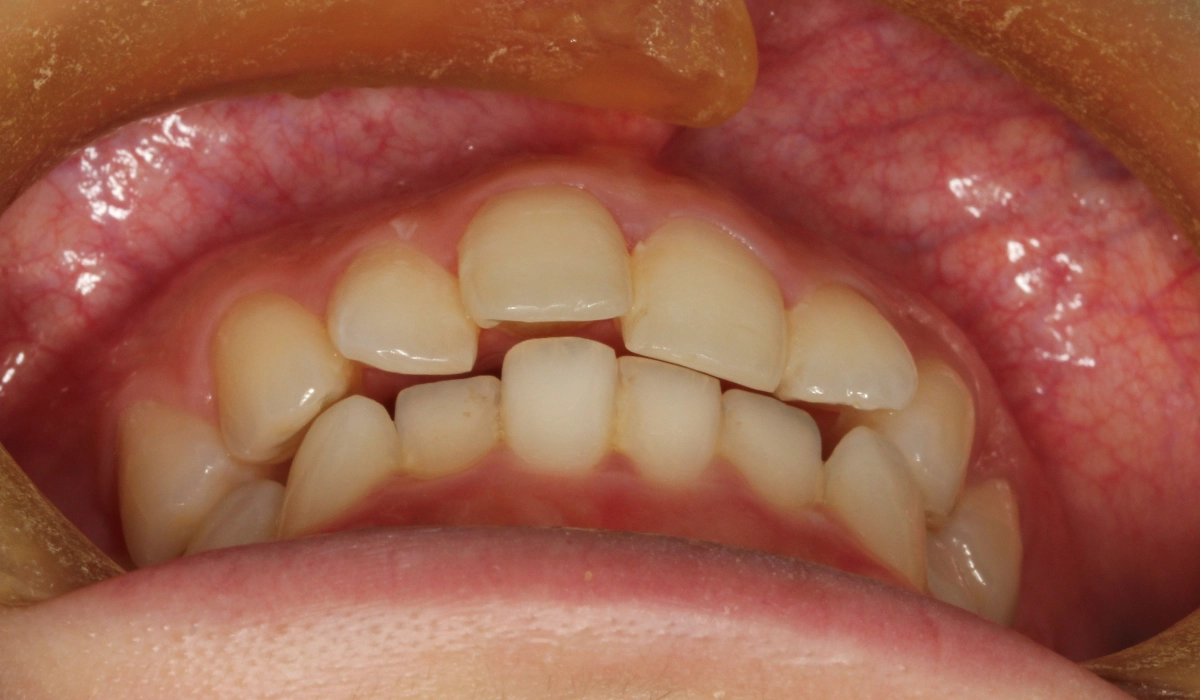

術前:前歯部

術前:正面

術前:右側

術前:左側